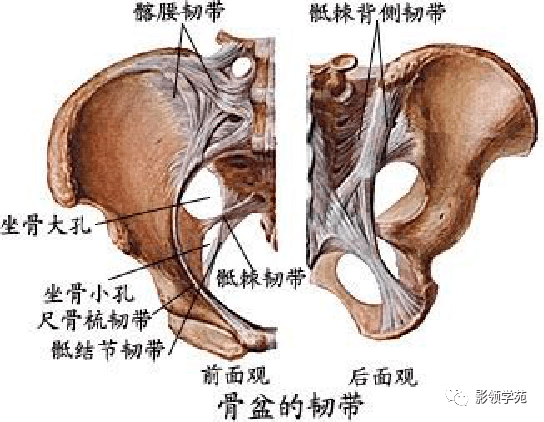

关节与韧带系统

韧带系统

关节与韧带系统

韧带系统